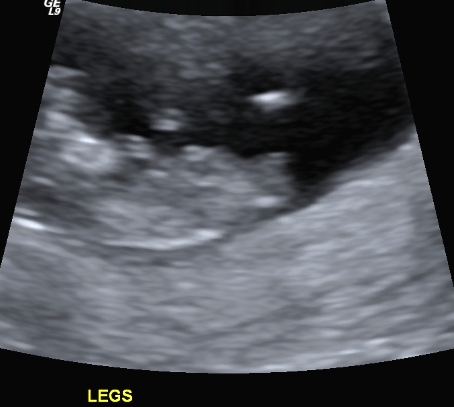

I finally managed to get hold of my u/s disc and have selected a few of the pics I think could have a nub in them (I'm still pretty hopeless at working out nubs).

There is only 1 pic from my 19 week scan that even comes remotely close to the bottom region and I'm pretty sure it is not a potty shot, just of legs from above I think??? (second last pic...biggest one)...I'm a little p'd off with the tech as I asked him to get a pic for me and he obviously didn't.

I have included quite a few from my early scan but bub was 11w4d so I understand prob slightly early still.